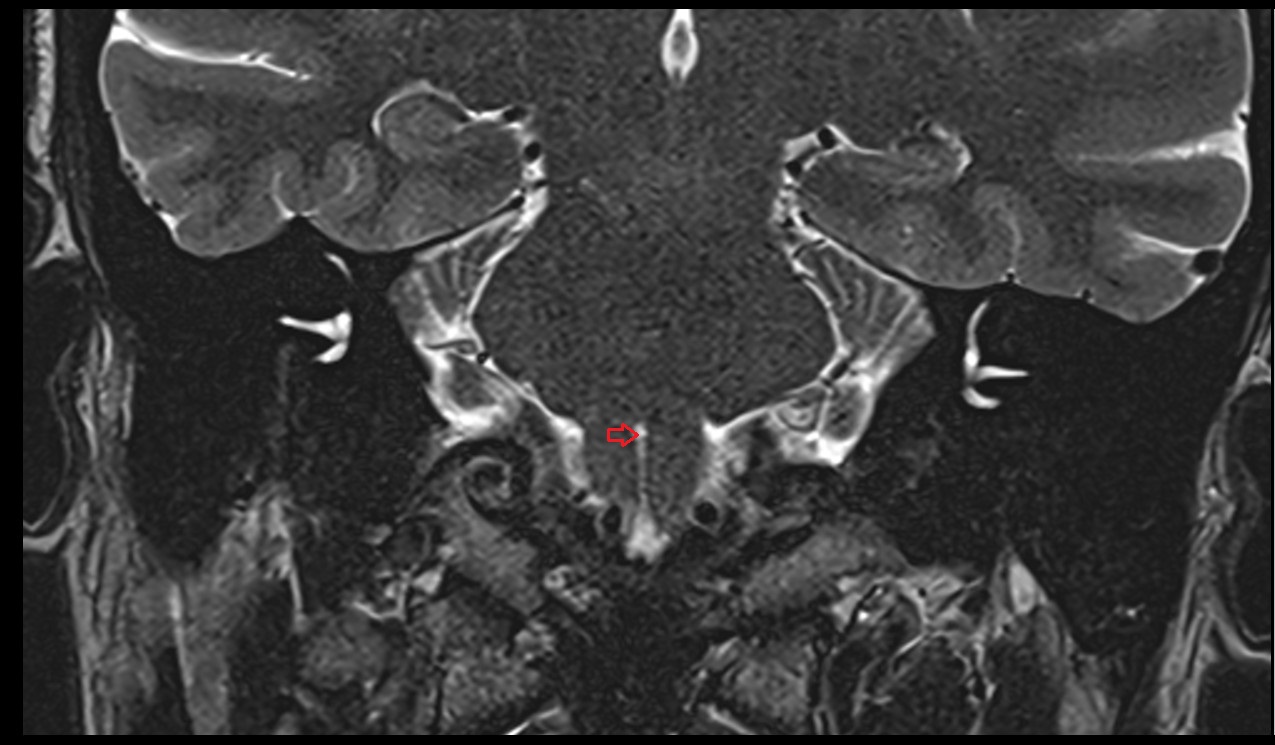

- Meckel’s cave (Trigeminal cave)